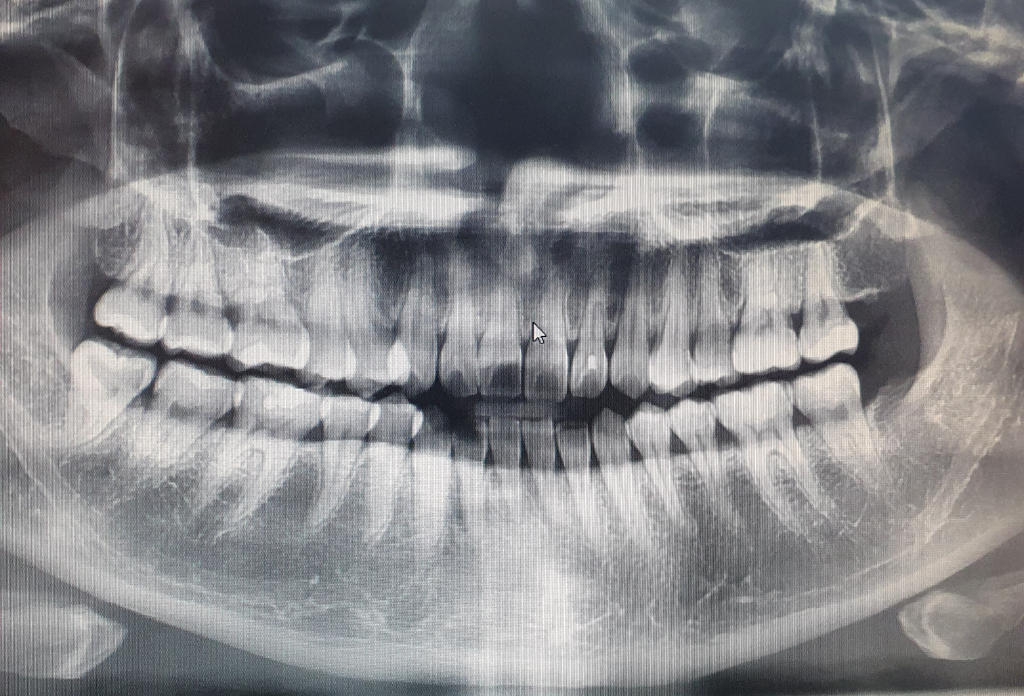

잇몸상태랑 전체적인 파노라마쫌 봐주세요ㅠㅠ 사랑니뿌리

파노라마랑 육안검진 동요도검사 다 이상이없다고햇습니다ㅠㅠ

파노라마상 하악잇몸이 대각선으로 내려간거같아서 물어봐요

우측 하악사랑니같은경우는 발치가 어려운케이스인가요?

파노라마 사진상으로는 잇몸이 내려가거나 잇몸뼈가 녹앗거나 하는건 보이지 않습니다. 관리를 잘하고 계신거 같습니다.

파노라마 사진으로만 봤을 경우에는 심각한 치주질환이 있어 보이진 않습니다.

1. 특별히 사진 상 잇몸뼈가 심하게 내려가거나 하는 잇몸질환이 심한 상태는 아닌 것으로 보여집니다

3. 우측하악 사랑니는 보통 정도의 발치 난이도로 생각됩니다.